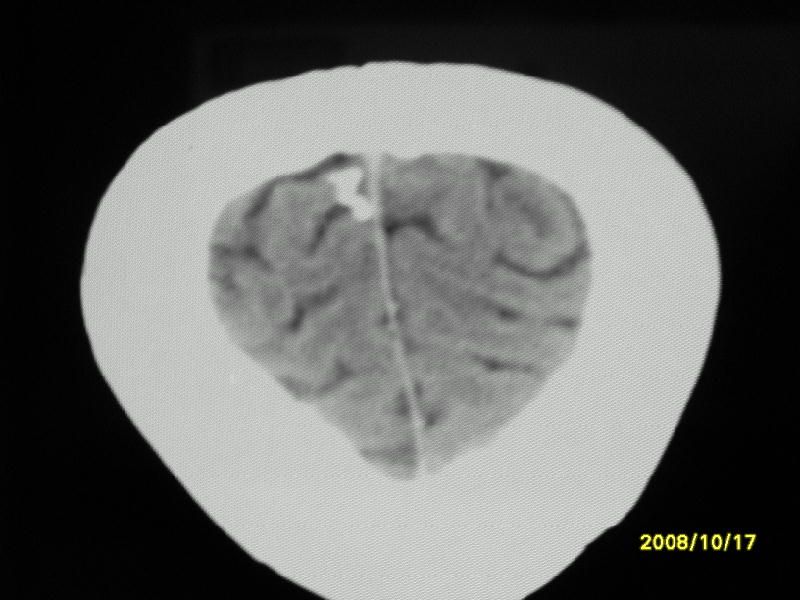

检查名称:     ct颅脑平扫           男     28岁

表现:左顶叶见斑点状致密影。边缘清,大小约0。3*1。0cm,余脑实质密度及灰白质结构示见异常。脑室系统大小,形态,密度未见异常。脑沟。脑裂。脑池未见异常密度影。中线结构无移位。

印象:左顶叶少许钙化灶

左顶叶见斑点状致密影。边缘清,大小约0。3*1。0cm,余脑实质密度及灰白质结构示见异常。脑室系统大小,形态,密度未见异常。脑沟。脑裂。脑池未见异常密度影。中线结构无移位。

印象:左顶叶少许钙化灶。